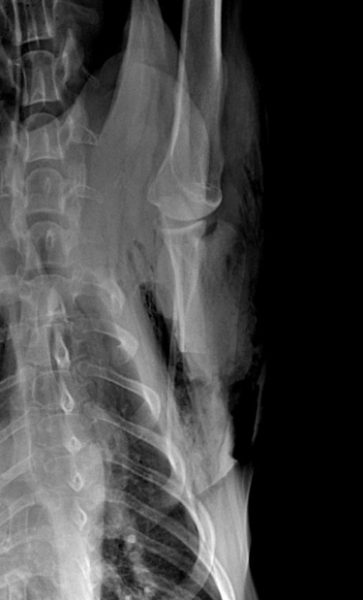

Un examen radiographique est réalisé sur animal vigile. Le coude gauche présente une dégradation arthrosique déjà avancée que l’on retrouve également sur le coude droit. Une déformation des tissus mous est visible en regard de la portion caudale de la scapula. L’articulation scapulo-humérale ne présente pas d’anomalie, seule la scapula présente des modifications de son architecture sur sa face interne avec une corticale effacée, une association d’ostéolyse et d’ostéoproduction (fig. 2 et 3).

Les radiographies post-opératoires permettent de vérifier les traits de section et l’exérèse large de la portion modifiée de la scapula (fig. 7 et 8). Un pansement compressif est mis en place autour du thorax afin de limiter la formation de sérosités. Il est laissé en place jusqu’au retrait des points 12 jours après l’intervention.